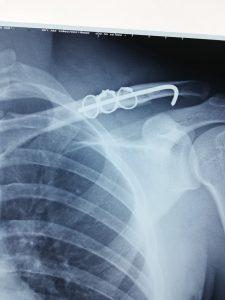

Ảnh. Bác sĩ TTYT Trà Cú phẫu thuật kết hợp xương

Trong tuần qua, đây là ca bệnh thứ 3 kết hợp xương thành công được bác sĩ của TTYT thực hiện tại phòng mổ của huyện, trong đó có 02 bệnh nhân bị gãy xương đòn và 01 bệnh nhân gãy xương ngón II, III bàn chân (T).